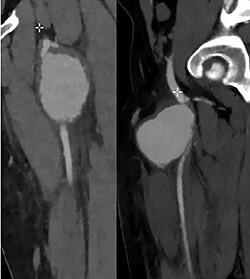

Spontaneous femoral artery pseudoaneurysm (PSA) is a rare disease and there are few reported cases. We report a case of a 17-year-old male with increasing left leg pain associated with swelling at the site of the pain. We observed a voluminous pulsatile mass. He had no history of trauma or surgery. Imaging confirmed a large PSA of the proximal portion of the left superficial femoral artery (SFA). The PSA was treated by resection of the aneurysm, reconstruction with inter-positional saphenous vein graft. Three months later; he came back to the emergency room for a pulsatile mass. The scan showed a PSA of his left SFA and a hematoma with active bleeding. It was treated surgically by resection of the aneurysm and reconstruction with graft.

自发性股动脉假性动脉瘤(PSA)是一种罕见疾病,报道的病例很少。我们报告一例17岁男性,左腿疼痛加重,疼痛部位伴有肿胀。我们观察到一个巨大的搏动性肿块。他没有外伤或手术史。影像学检查证实左股浅动脉(SFA)近端有一个大的PSA。通过切除动脉瘤、用大隐静脉间置移植进行重建来治疗该PSA。三个月后,他因搏动性肿块回到急诊室。扫描显示其左SFA有一个PSA和一个有活动性出血的血肿。通过切除动脉瘤并用移植物进行重建进行手术治疗。